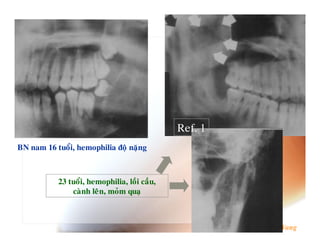

P$ # 4 $ 0 Ref. 1 #3 ; A B D 52N6 % 9 (4

0T9 L 9 @A9 UD 52N;52 V ; - . % ( . 52N ( 6 D % , ) 4 (4 6 7 6" ' F ' . %$ " . F :B R # $